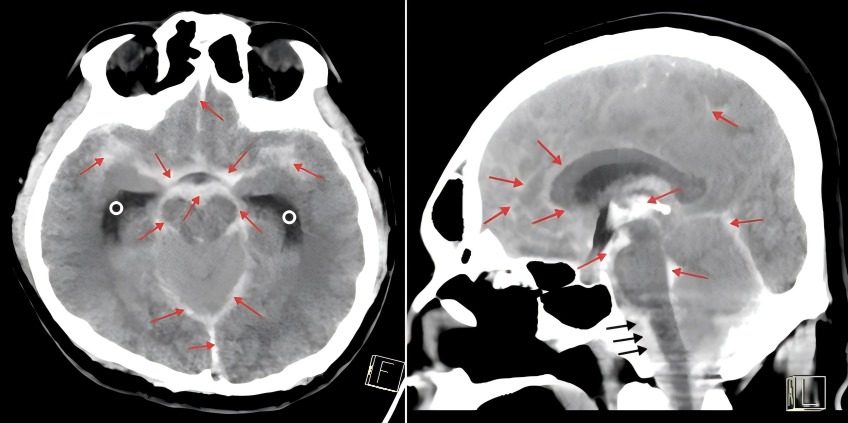

不能等,更不能退!团队果断决定——在呼吸机支持、持续用药和严密监护下“边抢救、边检查”。 头部CT迅速完成,结果令人揪心:蛛网膜下腔出血,合并脑积水,元凶直指死亡率极高的“椎动脉夹层动脉瘤”。

当务之急要解除脑积水,但难题接踵而至:患者生命体征极不稳定,任何搬动都可能再次心跳停止,根本无法进入手术室,甚至难以耐受麻醉。神经外科医学部负责人陈伟明团队当机立断——不等、不挪,就地手术!就在急诊抢救区,在呼吸机和升压药维持下,实施床旁脑室穿刺手术。在家属的充分信任下,床旁脑室置管手术迅速启动。

然而危险仍未解除,椎动脉夹层动脉瘤随时可能再次破裂,一旦再出血,几乎没有第二次生还机会。神经介入主任医师陈焕雄介入团队通过造影锁定椎动脉夹层动脉瘤,证实了术前推测,却陷入两难选择:必须植入支架预防再破裂,但植入后需抗血小板治疗,又会显著增加出血风险。在“止血”与“防梗”之间,团队精密测算,最终采用改良抗栓方案,在毫米级的血管内精准释放密网支架,封住了这颗“不定时炸弹”。